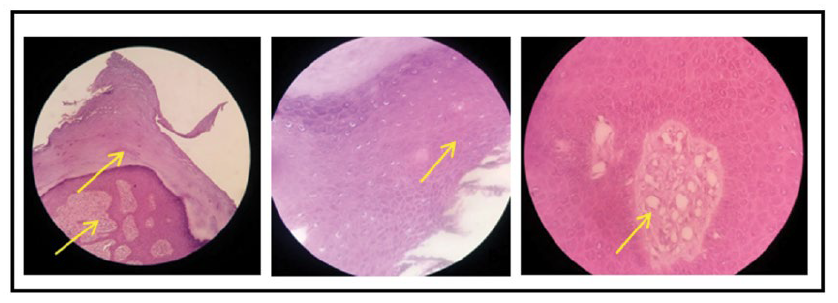

Gambar 7. Hasil pemeriksaan histopatologi yang diambil dari massa tumor yang tumbuh di sela jari kaki kanan pasien. Dari kiri ke kanan: pembesaran 10X tampak hiperkeratosis dan hiperplasia pseudoepiteliomatosa; pembesaran 40x tampak akantosis; pembesaran 100x tampak jaringan ikat fibrosa padat dikelilingi dengan banyak pembuluh darah.

Pemeriksaan penunjang elektrokardiografi (EKG) menunjukkan gambaran sinus ritme dengan heart rate (HR) 78 kali per menit, tanpa pembesaran ruang jantung. Pemeriksaan darah lengkap menunjukkan hasil normal. Pemeriksaan foto toraks tidak menemukan kelainan pada jantung dan paru. Dari pemeriksaan ultrasonografi (USG) abdomen tidak didapatkan kelainan pada organ intraabdomen. Pemeriksaan elektroensefalografi (EEG) tidak dilakukan karena ditolak oleh pasien. Tidak ditemukan kelainan pada pemeriksaan funduskopi. Pemeriksaan lengkap gigi geligi menemukan celah dental enamel dan fibroma gingival (Gambar 6). Hasil histopatologi dari fibroma ungual pada jari ke-5 kaki kanan tampak hiperkeratosis, akantosis, hiperplasia pseudoepiteliomatosa dan jaringan ikat fibrosa padat yang dikelilingi banyak pembuluh darah. Tidak didapatkan tanda-tanda keganasan, dengan kesimpulan sesuai dengan angiofibroma atau periungual fibroma (Gambar 7).